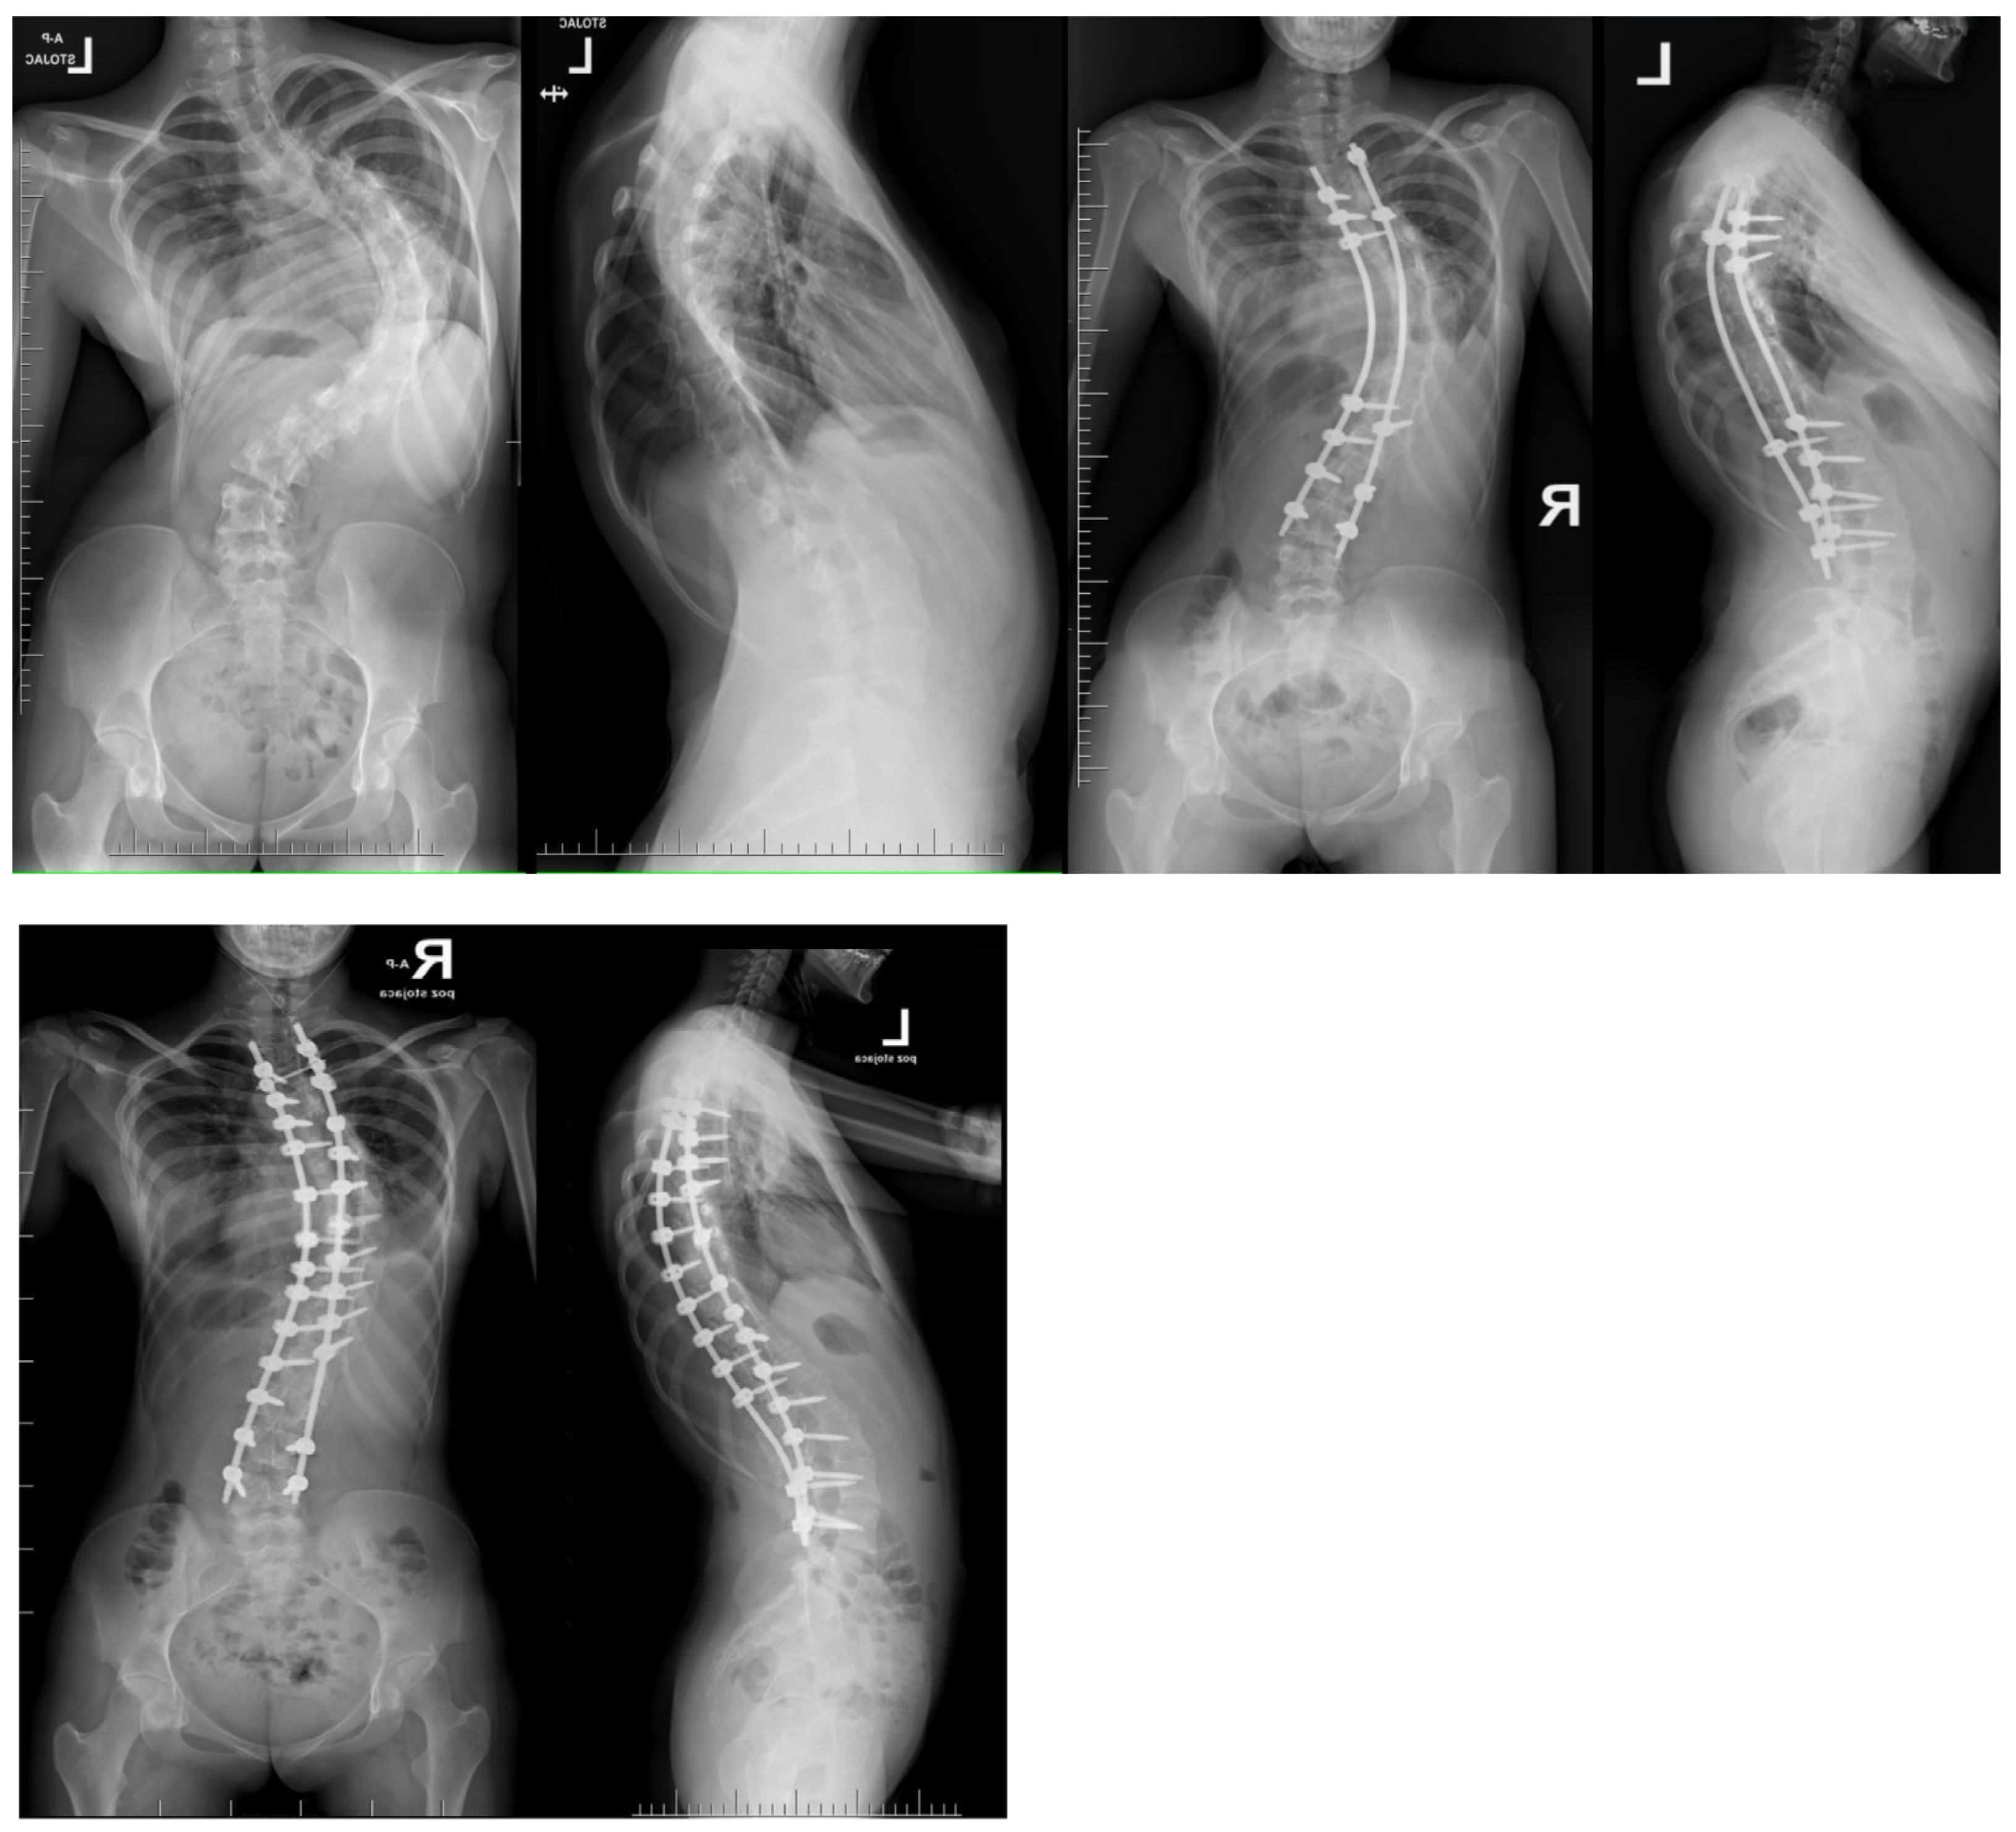

2. Material and Methods

8. Temporary Internal Distraction Rods

9. MCGR as Temporary Internal Traction

11. Author’s Preferred Technique